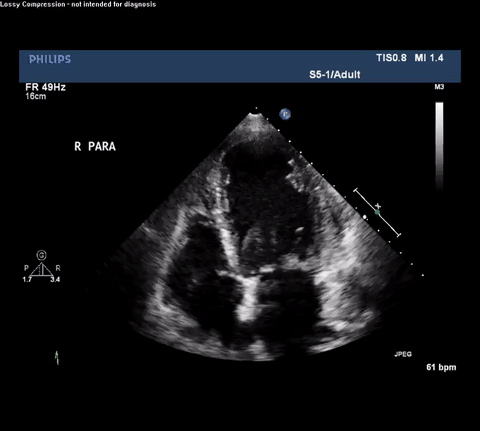

TTE Parasternal Short Axis View

Type A acute aortic dissection (TA-AAD). Cardiac POCUS imaging in the

parasternal long axis revealed the intima of the ascending aorta undulating in

and out of the left ventricular outflow tract throughout the cardiac cycle,

consistent with a TA-AAD.

Despite these shortcomings, cardiac POCUS can be performed quickly and does

not require either transport or IV contrast. This case illustrates how

intensivists performing routine cardiac POCUS exams need to be able to

identify both direct and indirect signs consistent with TA-AAD or else an

opportunity to provide expedited care may be missed. For example, it is

important to recognize the presence of an intimal flap which must be

differentiated from reverberation or mirror artifact originating from nearby

structures. Color Doppler can aid in identifying both true and false lumens

along with aortic regurgitation. Finally, depending on the clinical setting

other findings may be associated with TA-AAD and should raise concern for this

diagnosis including: bicuspid aortic valve, dilated aortic root, aortic

regurgitation and pericardial effusion.